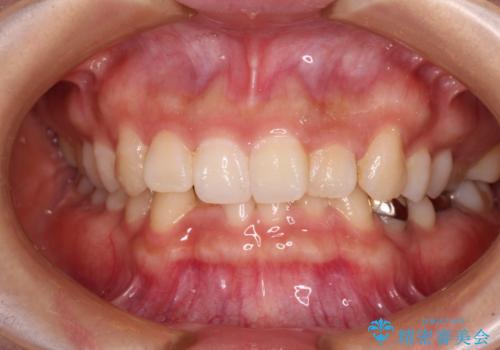

上下前歯の前歯と腫れやすい歯肉 インビザライン矯正で改善